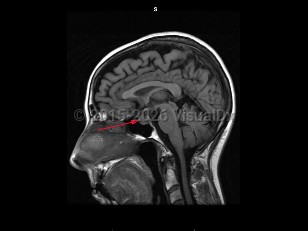

Craniopharyngioma

A craniopharyngioma is a brain tumor arising from pituitary embryonic tissue. It is typically suprasellar and has solid and cystic components. Age of onset can occur in childhood (about age 5-15) or adulthood (about age 50-70). There are adamantinomatous, papillary, and mixed types. Adamantinomatous tumors are more common in children and papillary tumors are more common in adults. A Rathke cleft cyst may develop from Rathke pouch if the pouch does not close normally.

Craniopharyngiomas are usually slow growing, and symptoms arise from compression of surrounding structures or increased intracranial pressure. Presenting symptoms include visual loss (most commonly superior temporal quadrantanopsia), headache, hormonal imbalances leading to delayed puberty in children, amenorrhea, hypersomnia, diabetes insipidus, and/or decreased libido. These tumors are usually benign with a good prognosis, but often recur when resection is incomplete.